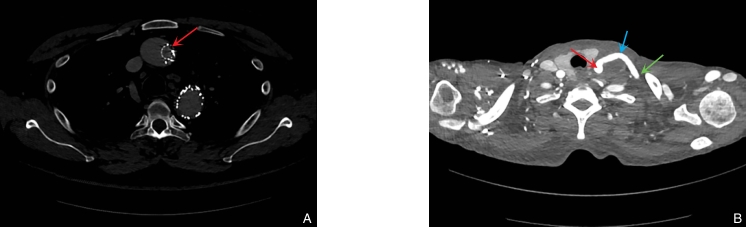

图2 代表性CT图像 A:TEVAR近端“日偏食样”结构(红色箭头);B:术后随访显示LCCA-LSA人工血管转流术后血流通畅(红色箭头指示LCCA,绿色箭头指示LSA,蓝色箭头指示桥血管)Fig.2 Representative CT images A: Partial solar eclipse-like configuration at the proximal landing zone after TEVAR (shown by red arrow); B: Follow-up imaging showing patent blood flow after LCCA-LSA bypass grafting (red arrow indicates the LCCA, green arrow indicates the LSA, and blue arrow indicates the bypass graft)